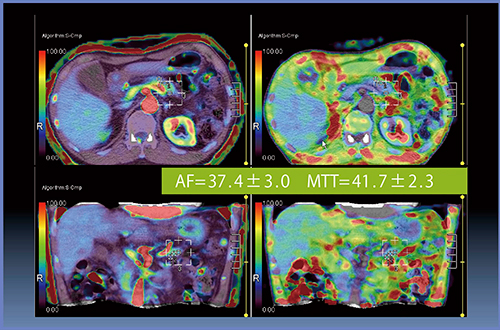

症例2は,膵頭部がんで術中にhard pancreasと判定され,術後膵液瘻なく経過した(図5)。Perfusion解析は,AF=37.4±3.0mL/min/100mL,MTT=41.7±2.3sとなった(図6)。

図6 症例2のPerfusion解析